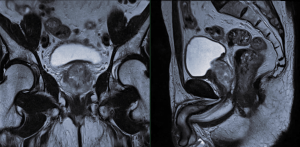

Read MoreProstate Cancer Awareness

Prostate cancer causes over 3000 deaths in Australian men each year. This makes prostate cancer the fourth main cause of...